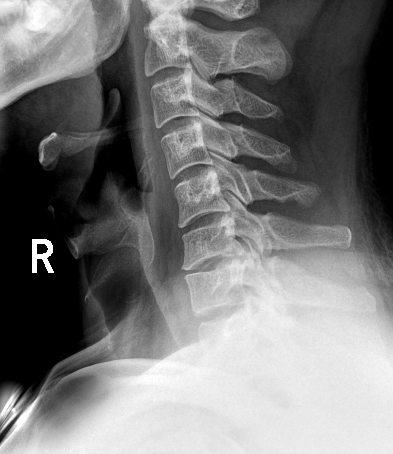

平板探测器

超高像素

高清点片